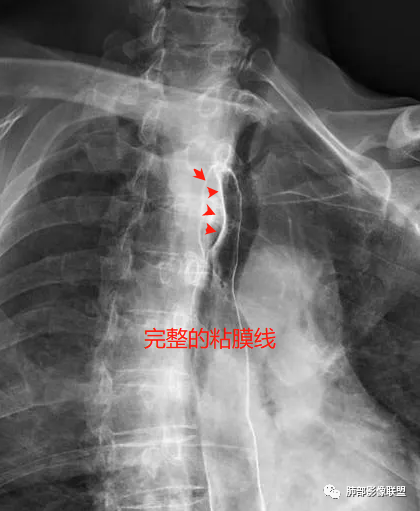

不管气管、食管都是粘膜下的

3.结合CT增强图像及食道钡餐影像(管壁整体柔软,粘膜线完整),提示肿块来源于粘膜下。